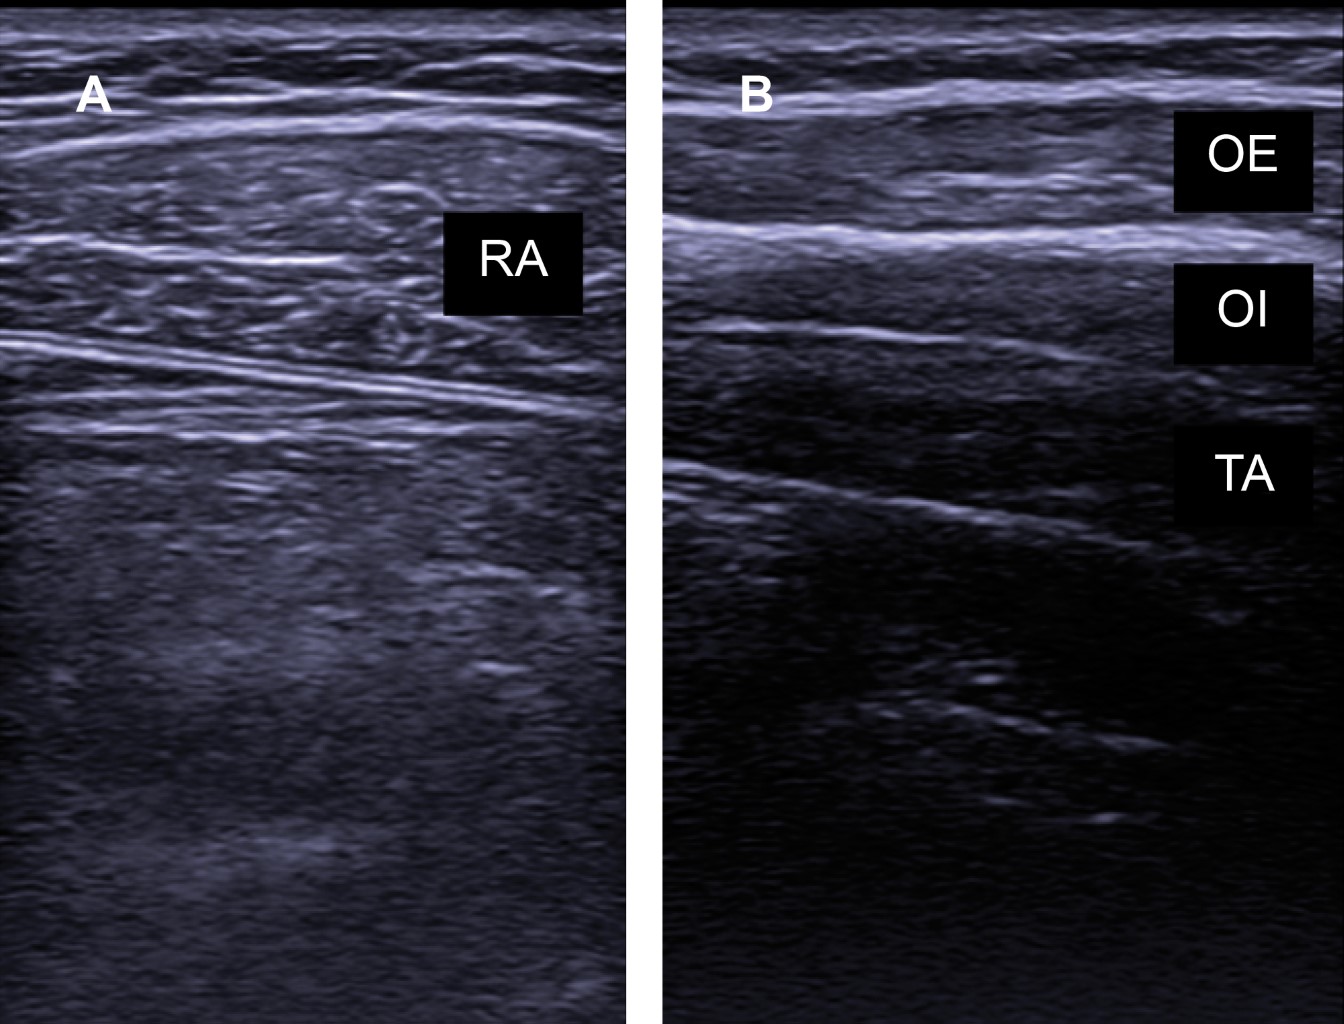

Los músculos espiratorios se encuentran en la pared abdominal, conformados por el transverso del abdomen, oblicuo interno y externo, además del recto abdominal (Figura 1). De manera secundaria puede haber participación de algunos músculos de la caja torácica.

Figura 1